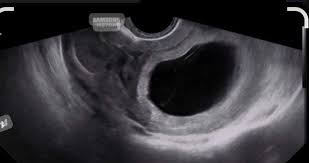

Un œuf clair est une situation où un follicule ovarien, qui devrait normalement contenir un ovocyte mature prêt à être fécondé, est vide ou ne contient pas d’ovocyte viable. L’œuf clair peut être détecté lors d’une échographie ovarienne, réalisée dans le cadre d’un suivi de l’ovulation ou d’un traitement de fertilité. Il est souvent observé lors de cycles où la stimulation ovarienne a été effectuée, comme lors des traitements de FIV ou d’insémination artificielle.

Dans une ovulation normale, un follicule se développe, libère un ovocyte au moment de l’ovulation, et cet ovocyte est alors prêt à être fécondé. Lorsque le follicule est « clair », cela signifie qu’il n’a pas réussi à libérer un ovocyte viable, ou qu’il n’y a pas d’ovocyte à l’intérieur, même si le follicule semble bien se développer sur le plan échographique.